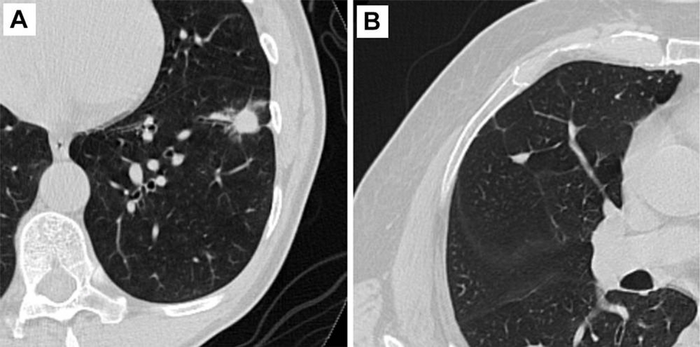

CHICAGO – Diagnosing early-stage lung cancer with low-dose CT screening drastically improves the long-term survival rate of cancer patients, according to a large-scale, 20-year international study being presented next week at the annual meeting of the Radiological Society of North America ( RSNA ).

The study found that the 20-year survival rate was 80% for the 1,285 I-ELCAP participants who were diagnosed with early-stage lung cancer. The survival rate for both the 139 participants with nonsolid cancerous lung nodules and the 155 participants with nodules of part-solid consistency was 100%. For the 991 participants with solid nodules, the survival rate was 73%.

The researchers also estimated survival for clinical Stage IA lung cancers and for resected pathologic stage IA lung cancers measuring 10mm or less in average diameter of length and width on the same CT image. A stage I lung cancer is a very small tumor that has not spread to any lymph nodes.

Lung cancer survival for clinical Stage IA participants was 86%, regardless of consistency. For participants with pathologic Stage IA cancers of 10 mm or less, the 20-year survival rate was 92%.